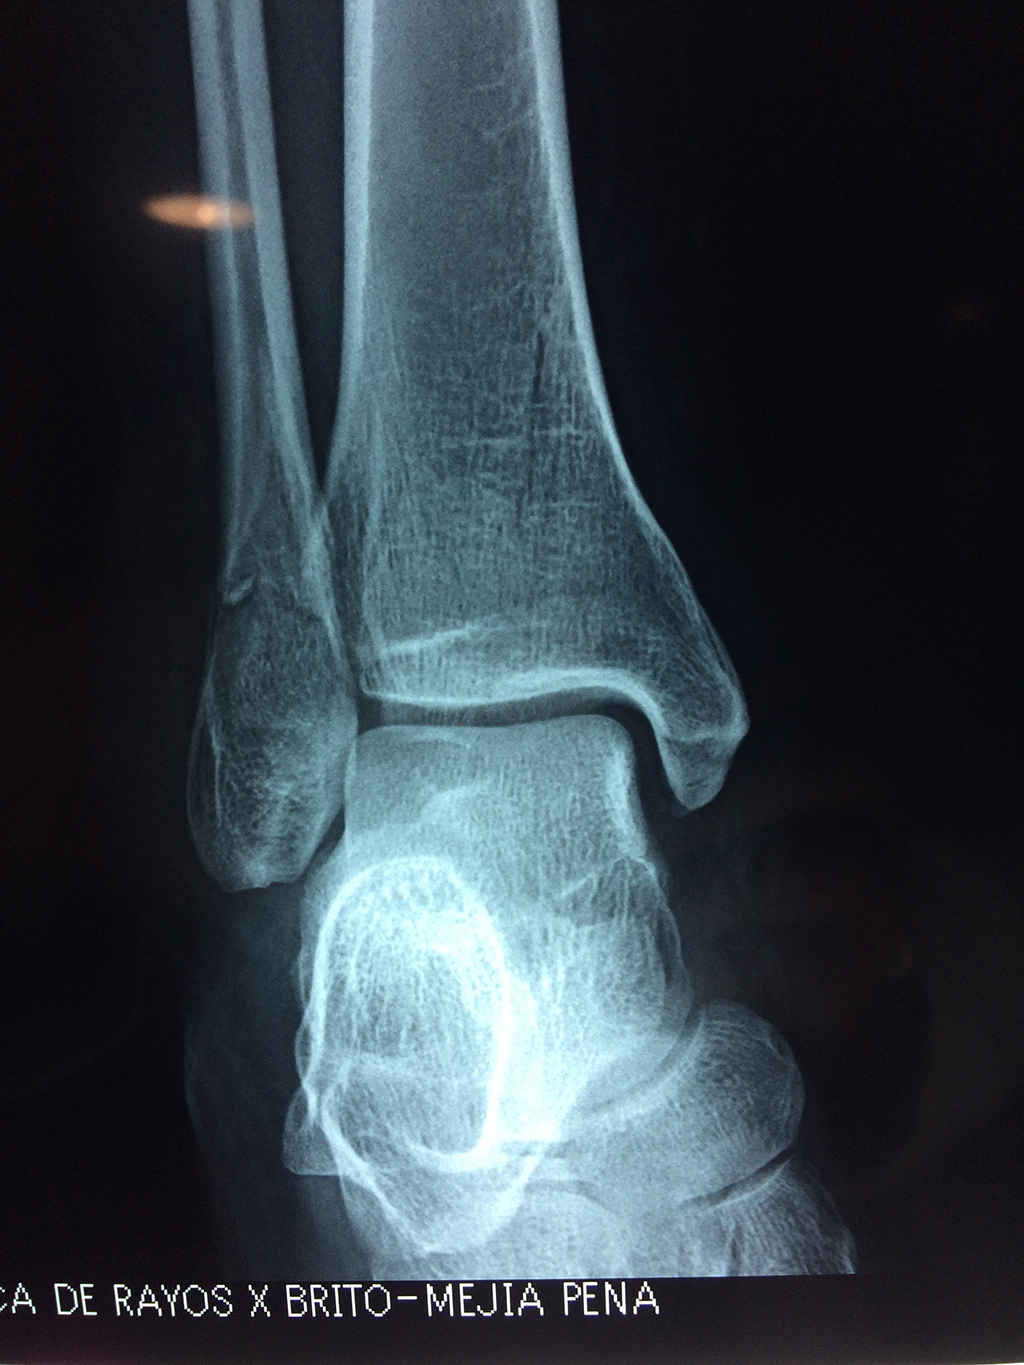

Una fractura de tobillo es la rotura de uno o más de los huesos del tobillo. Estas fracturas pueden ser:

- Parciales (el hueso está sólo parcialmente fisurado, no del todo).

- Completas (el hueso está perforado y está en 2 partes).

- Producirse en uno o ambos lados del tobillo.

Algunas fracturas de tobillo pueden requerir cirugía si:

- Los extremos de los huesos están desalineados entre sí (desplazados).

- La fractura se extiende hasta la articulación del tobillo (fractura intra-articular).

- Los tendones o ligamentos (tejidos que sujetan los músculos y los huesos entre sí) están rotos.

- El médico cree que sus huesos probablemente no sanen apropiadamente sin cirugía.

- El médico considera que la cirugía puede permitirle una recuperación más rápida y confiable.

- En los niños, la fractura involucra la parte del hueso del tobillo donde el hueso está creciendo.

Cuando se necesita cirugía, es probable que esta implique el uso de clavijas de metal, tornillos o placas para sostener los huesos en su lugar mientras la fractura se consolida. Los elementos de soporte pueden ser temporales o permanentes.